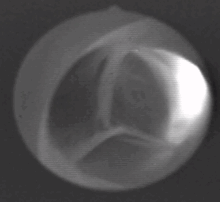

يتكون الصمام من ثلاث شُرَف (باللاتينية: Valvulae) تلتقي معاً على شكل نجمة ثلاثية، تحوي هذه الشرف على مخارج الشريانات التاجية.

يقع الصمام الأبهري عند مخرج البطين الأيسر وعند بداية الشريان الأبهري فيما يسمى بجيب الأبهر، وهو الجزء الأول من الشريان. يتكون الصمام الأبهري من ثلاث شُرَف (أو جيوب) نسيجية وتنبثق عما يسمى بقاعدة القلب أو المستوى الذي تقع فيه باقي صمامات القلب (انظر الصورة).

شُرَف الصمام على شكل جيوب تخرج من حلقة دائرية من النسيج الضام، تلتقي أطرافها الحرة في المنتصف لتشكل حين انغلاقها شكل نجمة ثلاثية (تشبه نجمة المرسيدس)، وتكون أطرافها سميكة لتضمن الانغلاق المتكامل. شُرَف الصمام الأبهري هي: